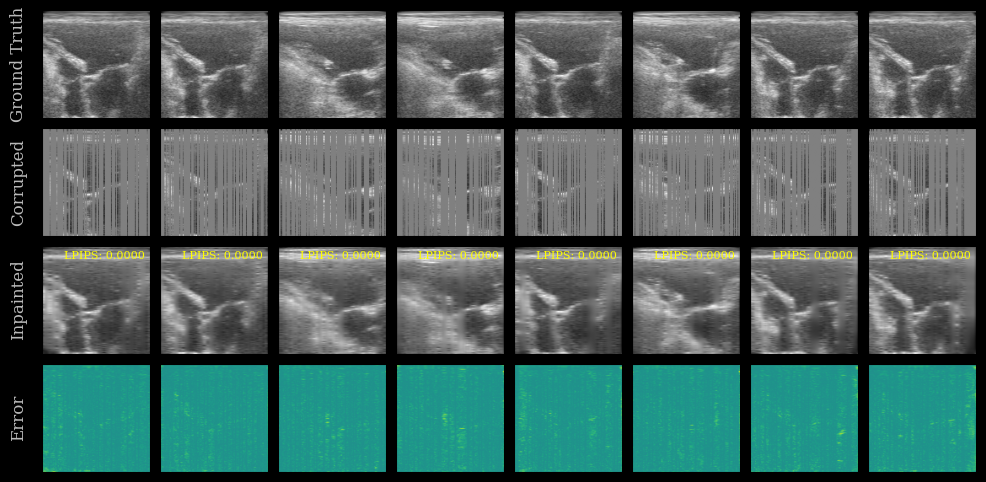

We plot the ground truth, corrupted, inpainted, and error images. The LPIPS score is shown on each inpainted image. Note that this model was trained on the EchoNet-Dynamic dataset, whereas we are testing now on the CAMUS dataset.

[10]:

error = ops.abs(batch - inpainted)

imgs = ops.concatenate([batch, corrupted, inpainted, error], axis=0)

imgs = ops.convert_to_numpy(imgs)

cmaps = ["gray"] * (3 * n_imgs) + ["viridis"] * n_imgs

fig, _ = plot_image_grid(

imgs,

vmin=-1,

vmax=1,

ncols=n_imgs,

remove_axis=False,

cmap=cmaps,

figsize=(n_imgs * 2, 6),

)

titles = ["Ground Truth", "Corrupted", "Inpainted", "Error"]

for i, ax in enumerate(fig.axes[: len(titles) * n_imgs]):

if i % n_imgs == 0:

ax.set_ylabel(titles[i // n_imgs])

# Show LPIPS score on each inpainted image

for ax, lpips_score in zip(fig.axes[n_imgs * 2 : 3 * n_imgs], lpips_scores):

ax.text(

0.95,

f"LPIPS: {float(lpips_score):.4f}",

ha="right",

va="top",

transform=ax.transAxes,

fontsize=8,

color="yellow",

plt.show()